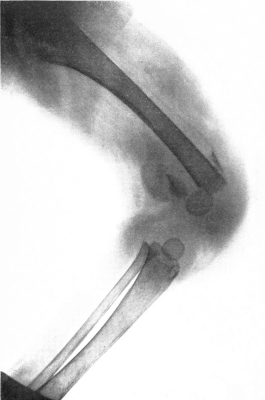

| 6. | Subperiosteal hemorrhage and separation of epiphysis. Roentgenogram | 109 |

| 7. | Complete restitution of epiphysis without deformity. Roentgenogram | 109 |

| 16. | Subperiosteal hemorrhage and separation of epiphysis. Roentgenogram | 192 |

| 17. | Periosteal “tags” and “streamers.” Roentgenogram | 193 |